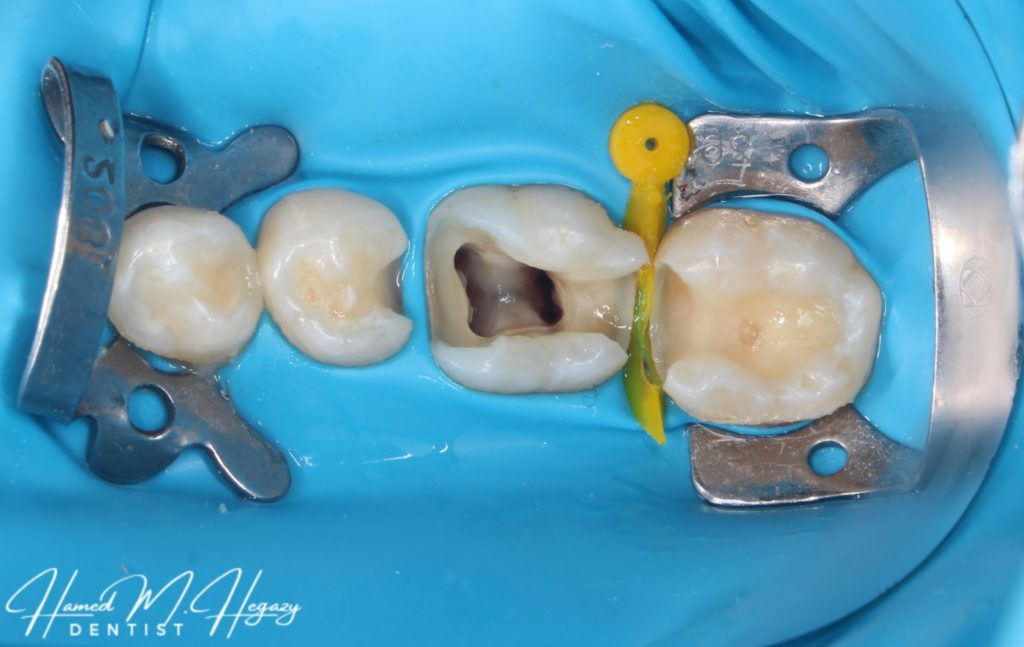

Access cavity

5 canals in lower 6

Middle Mesial canal